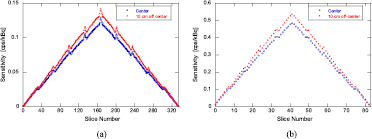

The absolute system sensitivity values were corrected for 176Lu background, and only the activity located in the FOV was taken into account. In the HR and HS-modes, the absolute system sensitivity values were 21.4 cps kBq−1 (2.14%) and 23.7 cps kBq−1 (2.37%) for the center and 10 cm off-center positions of the FOV, respectively (table 3). The background count rate for true coincidence was 105 cps. The distributions of the slice sensitivity for the center and 10 cm off-center positions for the HR and HS-modes are shown in figure 9. The distributions for both HR and HS-modes took on a triangular shape, because almost all LORs in a ring difference were used. The maximum sensitivity per slice in the HS-mode was approximately four times higher than that in the HR-mode, since the defined slice thickness (2.4 mm) in the HS-mode was four times thicker than that (0.6 mm) in the HR-mode.

Figure 9. Distributions of the slice sensitivity for the center and 10 cm off-center positions for the (a) high-resolution (HR)-mode and (b) high-speed (HS)-mode.

Download figure:

Standard image High-resolution image3.5. Phantom studies